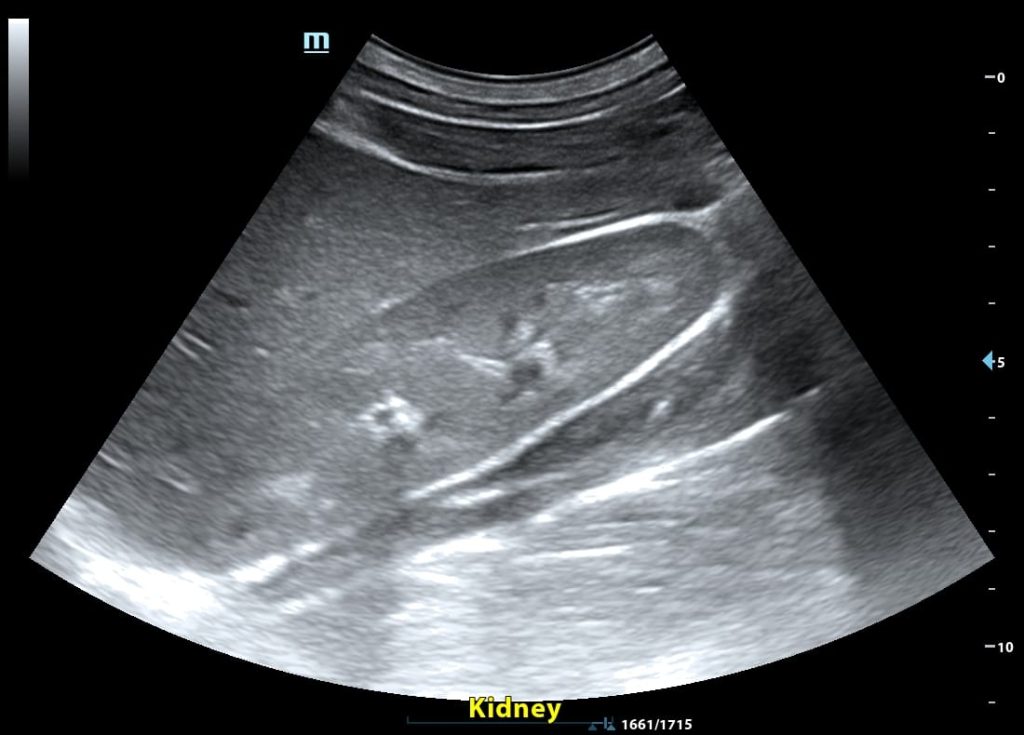

Υπερηχογράφημα νεφρών. Το υπερηχογράφημα των νεφρών, ουροδόχου κύστεως και προστάτη είναι πολύ χρήσιμη εξέταση

Υπερηχογράφημα νεφρών-ουροδόχου κύστεως και προστάτη

Το υπερηχογράφημα νεφρών είναι μια απλή και αναίμακτη εξέταση για την εκτίμηση του μεγέθους των νεφρών και την αξιολόγηση του συλλεκτικού συστήματος, όταν ελέγχονται και οι ουρητήρες και η ουροδόχος κύστη.

Το υπερηχογράφημα των νεφρών προσφέρει σημαντικές πληροφορίες για υποκείμενα νοσήματα των νεφρών και της αποχετευτικής μοίρας του ουροποιητικού συστήματος, συμπεριλαμβανομένου του προστάτη αδένα στους άνδρες, όταν ελέγχεται και ο προστάτης στους άνδρες.